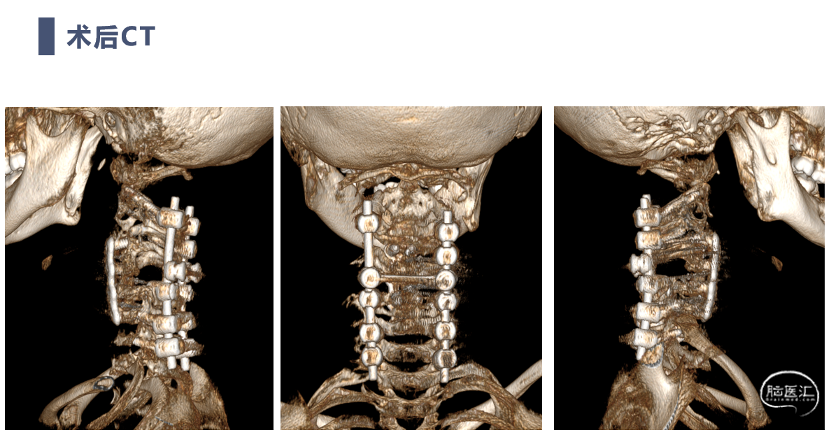

术后CT

前路手术完成后,翻身行后路C2-C7置钉

C4及C5侧块无法置钉,双侧C5放置椎板钩增加把持力

双向牵引后,患者后方小关节仍存在一定绞锁,首先行后路手术,充分松解后方绞锁的关节突。再行前路手术,矫正后凸畸形,前路手术时因患者骨量极少,单纯前路螺钉复位力量弱,借助提拉工具完成良好复位。最后翻身行后路手术完成C2-7后路固定,因患者多数侧块发育异常,双侧C4-5无法置钉,应用椎板钩固定,双侧C2椎弓根直径只有3.2mm,但成功置入了两颗3.5mm螺钉。

术后复查患者复位满意,颈痛及神经症状消失,但此类患儿骨性结构发育异常,需要密切随诊,观察有无近端或远端交界性后凸发生。